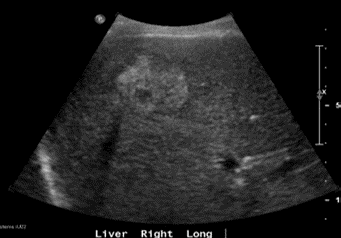

During this admission, an ultrasound hepatobiliary system (US HBS) was performed due to complaints of pain over the right hypochondrium area. The US HBS (Figure 1) showed presence of a heterogeneously echogenic indistinct mass in the right lobe of the liver measuring 4.7 x 3.8 x 3.9cm with interval vascularity. Another homogenously hypoechoic nodule in segment VI was also seen, measuring 1.1 x 0.9 x 0.8cm. Due to the nature of the lesions, they remain indeterminate, and thus, the patient was referred to the hepatobiliary surgery for further management. His alpha-feto protein level was 13.03ug/L (1.00-10.00ug/L).

Figure 1: Ultrasound hepatobiliary system showing the 4.7 x 3.8 x 3.9 cm hyperechoic mass.